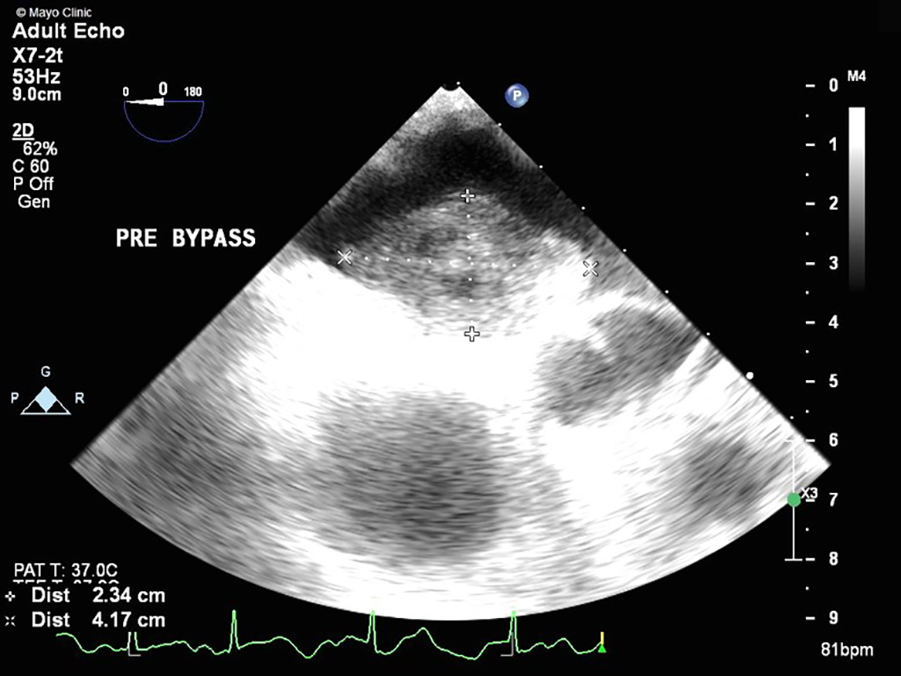

Figure 1

TEE showing a large mass (2.3 cm × 4.2 cm) with attachment to the left atrial side of the atrial septum.

Her physical examination was unremarkable, as exemplified by the fact that her heart sounds were normal. A brain magnetic resonance imaging (MRI) did not show signs of ischemia or prior infarction. An echocardiogram in the ED demonstrated a left atrial mass with a broad base attachment to the atrial septum (Figure 1) that extended from the opening of the pulmonary veins to the mitral annulus. Subsequent investigation with coronary computed tomography angiography (CCTA) revealed a 41 mm × 27 mm × 33 mm broad-based lobulated mass in the left atrium that extended onto the mitral annulus (Figure 2). The mass was isointense on T1-weighted images and hyperintense on T2-weighted images and showed restricted diffusion (Supplementary Figure S1). There was heterogeneous enhancement on both early and late postcontrast images. The findings were compatible with a cardiac myxoma (Supplementary Video S1).

Myxomas are often initially diagnosed by echocardiography. The classic presentation is a mobile mass on a stalk arising from the atrial septum. In our patient, a TEE was done prior to surgery to assess hemodynamic function. A cavitated sessile mass arising from the atrial septum was seen. The mass did not have a stalk and exhibited contrast within the body of the tumor. The lack of a stalk from which the tumor arose and its cavitated appearance were atypical for a myxoma, warranting further investigation and planning prior to resection. The mass also extended upward into the right pulmonary veins, which is extremely uncommon. Cardiac MRI (CMRI) often complements echocardiography and offers improved tissue characterization, with cardiac myxomas typically demonstrating hypointensity on T1 images, hyperintensity on T2 images, and little to no perfusion or late enhancement (5). T1- and T2-weighted double-recovery sequences aid tissue characterization. Furthermore, cine cardiac imaging holds great importance in evaluating atrial myxomas because of their high mobility and their tendency to prolapse through the atrioventricular valve during diastole (6). Contrast-enhanced sequences are crucial in distinguishing myxomas from thrombus, as myxomas typically exhibit minimal or nil enhancement during first-pass perfusion, yet display a more heterogeneous enhancement pattern on late gadolinium enhancement (LGE) imaging (7). In our case, the patient's cardiac MRI scan did show findings consistent with those of a myxoma, but it revealed more enhancement than is typical. Cardiac MRI has shown remarkable accuracy in identifying cardiac masses and effectively differentiating between benign and malignant tumors. However, relying solely on MRI has been associated with occasional instances of inaccurate diagnosis. Therefore, adopting a multimodal imaging approach comprising echocardiography, MRI, CT, and possibly positron emission tomography (PET) imaging offers an optimal approach for a comprehensive evaluation and stratification of cardiac masses (8). Given the atypical characteristics and location of our patient's left atrial mass, a CT angiogram with a 3D reconstruction of the heart depicting the mass was requested to guide the diagnosis and surgical planning. The mass was heterogeneously enhancing and polypoid in shape. The mass did not infiltrate or invade surrounding structures. This observation holds considerable significance as it reduces the likelihood of the tumor being a malignant one (9). However, it did extend to the ostium of the right superior pulmonary vein, occluding it during atrial systole. It is hard to ascertain whether the mass was the source of our patient's symptoms, but these findings could potentially explain the patient's orthostatic syncope and dizziness. A case report in the literature describes a patient presenting with syncope and dyspnea, who was found to have a left atrial myxoma extending into and occluding the left pulmonary veins and causing pulmonary infarction (10). However, in our patient, the mass did not extend or occlude the mitral valve, which made it feasible to adopt a robotic approach. Furthermore, the mass received blood supply from the small sinoatrial node branch of the right coronary artery. This was visualized precisely and with high spatial resolution on the 3D-printed model, which also showed the extent of expansion of the mass into the right upper pulmonary veins (Figure 4). The printed model also provided for visualization of the best approach to enter the left atrium without disruption of the mass. A possible implication of this occurrence is the formation of a fistula between the sinoatrial nodal artery and the right atrium after surgical resection of the atrial myxoma. For this reason, special attention should be paid to ligating neovascularized branches feeding myxomas during the surgical procedure (11).